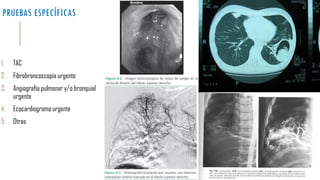

PRUEBAS ESPECÍFICAS

1.TAC

2.Fibrobroncoscopia urgente

3.Angiografía pulmonar y/o bronquial urgente

4.Ecocardiograma urgente

5.Otras